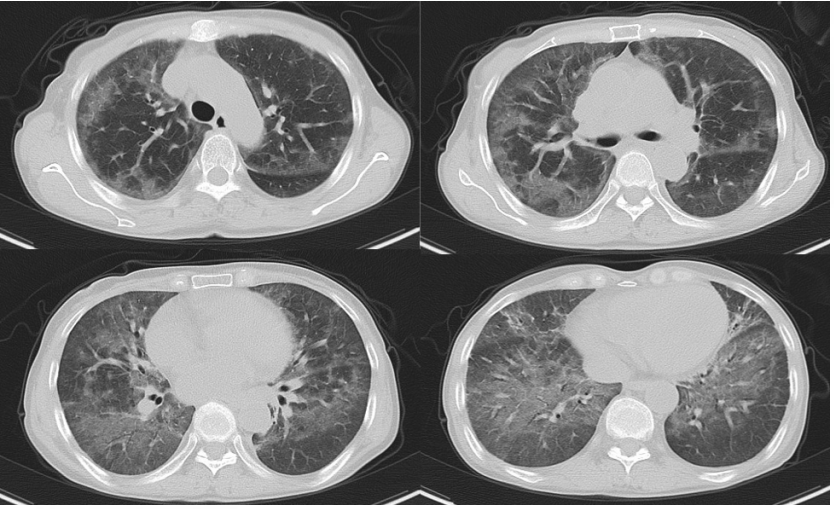

病例2:肾移植术后半年,发热3天。影像学表现并不严重(图10)。入院后完善NGS,耶氏肺孢子菌序列数330000。入院后即予SMZ+卡泊芬净+甲泼尼龙治疗,但病情仍然加重,入院10天转ICU,影像学持续进展(图11)。患者入ICU后NGS结果回报耶氏肺孢子菌序列数843433周后死亡。

图片

10  患者入院胸部CT

11  患者病程中胸部CT变化情况

文献报道,SMZ可以结合二氢叶酸合成酶(DHPS)基因位点从而抑制DHPS的合成TMP可以结合二氢叶酸还原酶(DHFR)基因位点从而抑制DHFR的合成达到杀灭耶氏肺孢子菌的作用国外学者1998年即发现了耶氏肺孢子菌DHPS基因突变,且接受磺胺及氨苯砜预防患者突率远高于未预防患者(70.6%:16.6%);Van Hal等发现DHPS基因型密码子55和57突变与疾病严重程度相关,与野生型相比,患者有创通气的比例更高,且临床结局更差。这一案例提醒我们,对于SMZ治疗效果不佳的患者,应及时进行BALF二次送检,若耶氏肺孢子菌丰度值依然较高,需警惕磺胺耐药的发生,及时更换治疗方案